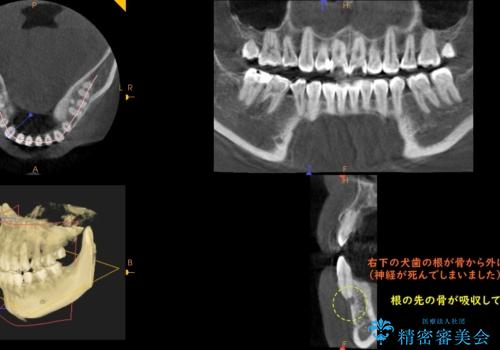

CTでみたところ、下の犬歯が内側に倒れこんでおり、根の先が顎の骨から出かかっている状態でした。おそらくその影響で犬歯の神経が失活してしまったのであろうと思われます。(フェネストレーションといいます)

検査した結果下の両側の犬歯の神経が失活しており、根の治療が必要な状態でした。

矯正専門の医院でCTまで完備しているというのはなかなか施設の規模として難しいと思います。

また、矯正医が気付かずにすき間をとじようとして犬歯が倒れてしまうと今回のようなことが後々時々起こります。

一見歯がきれいに並んでいても、中の根の先の位置までしっかり矯正治療で丁寧に動かさないと、今回のように神経が失活するリスクがあるので、注意が必要です。